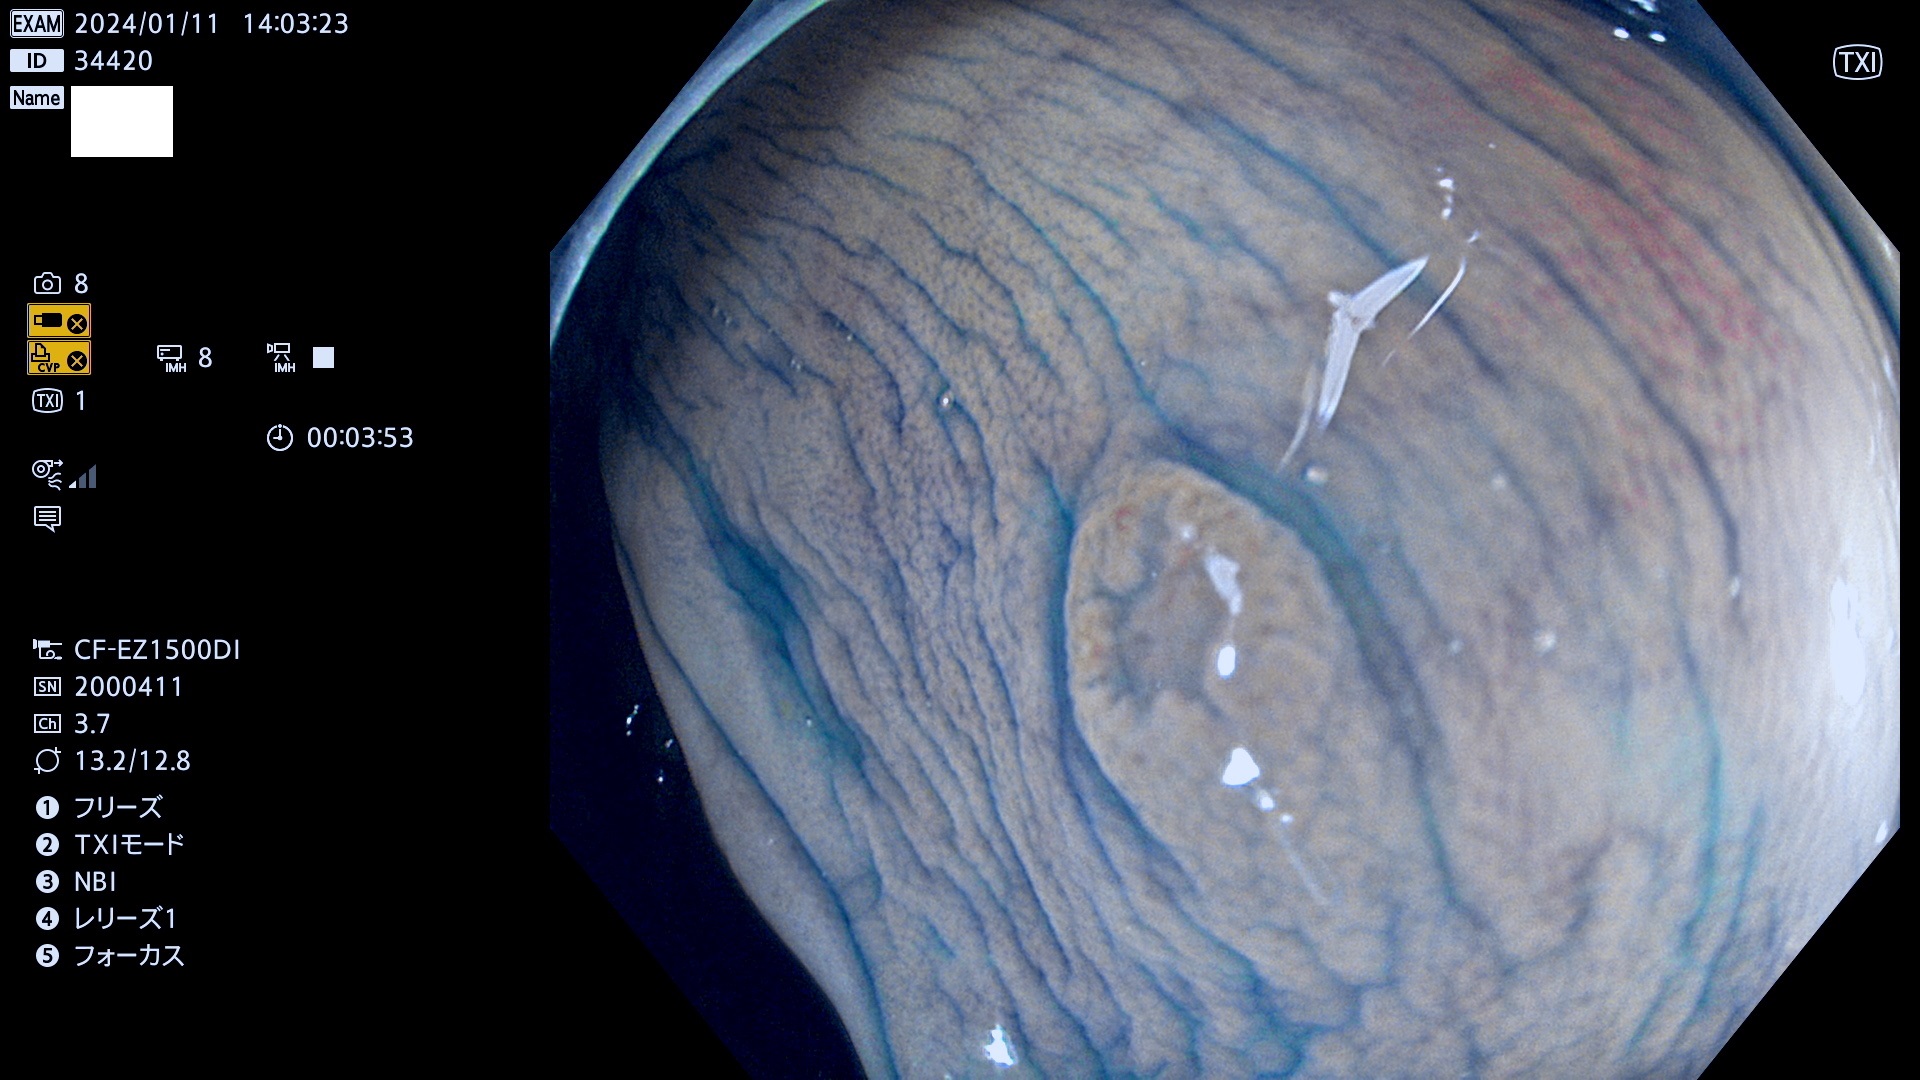

表面型腺腫(Flat Adenoma)の中で、完全に平坦な物をUb、陥凹している物をUcと呼びます。平坦隆起型(Ua)よりも、発見が難しく危険な病変です。

毎週の検査(木・金・土・日)に発見されたUb、Uc型・腺腫を、その週の日曜の夜にUPし1週間、提示します。

抽出の対象期間 2024年1月11日(木))〜1月14(日)の4日間(40件の検査)9件